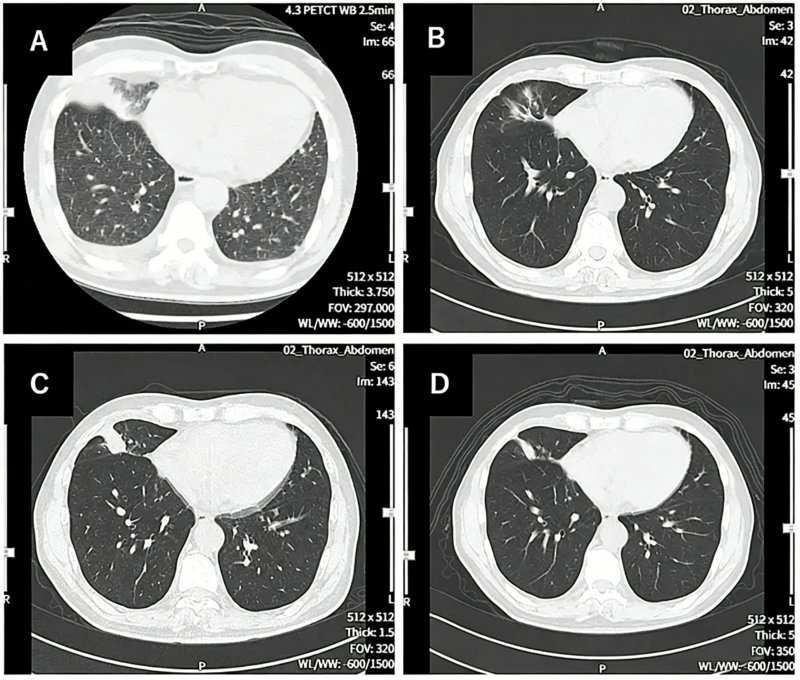

其中一位69岁的晚期非小细胞肺癌患者,经历了多线治疗失败,但在接受3个周期的联合治疗后,右肺的原发病灶基本消失,左肺和纵隔淋巴结的转移灶也显著退缩,达到了临床上的“部分缓解(PR)”。整个过程仅仅出现轻微发热等可控反应。这对于一个终末期患者而言,无异于绝处逢生。

在启动了WT1-DC疫苗联合多西他赛及靶向药治疗后,奇迹发生了:无进展生存期(PFS)超过了577天!不仅肺部原发灶缩小了70%以上,全身的转移灶也出现了显著的消退。 肿瘤标志物断崖式下降,患者的体力恢复,能够重新回归正常生活。疫苗极大地优化了患者的免疫微环境,延长了化疗的有效窗口期。

前沿医学的临床转化正在加速。很多上述提到的突破性疫苗及联合疗法,目前正在国内开展严谨的临床研究,如果想更详细的了解,可以将近期的详细病历资料(包括确诊病理报告、基因突变检测报告、最新的影像学CT/PET-CT报告及近期的出院小结等)进行整理,提交至医学部进行初步评估, 多一次问询,或许就能为生命打开一扇全新的窗户。